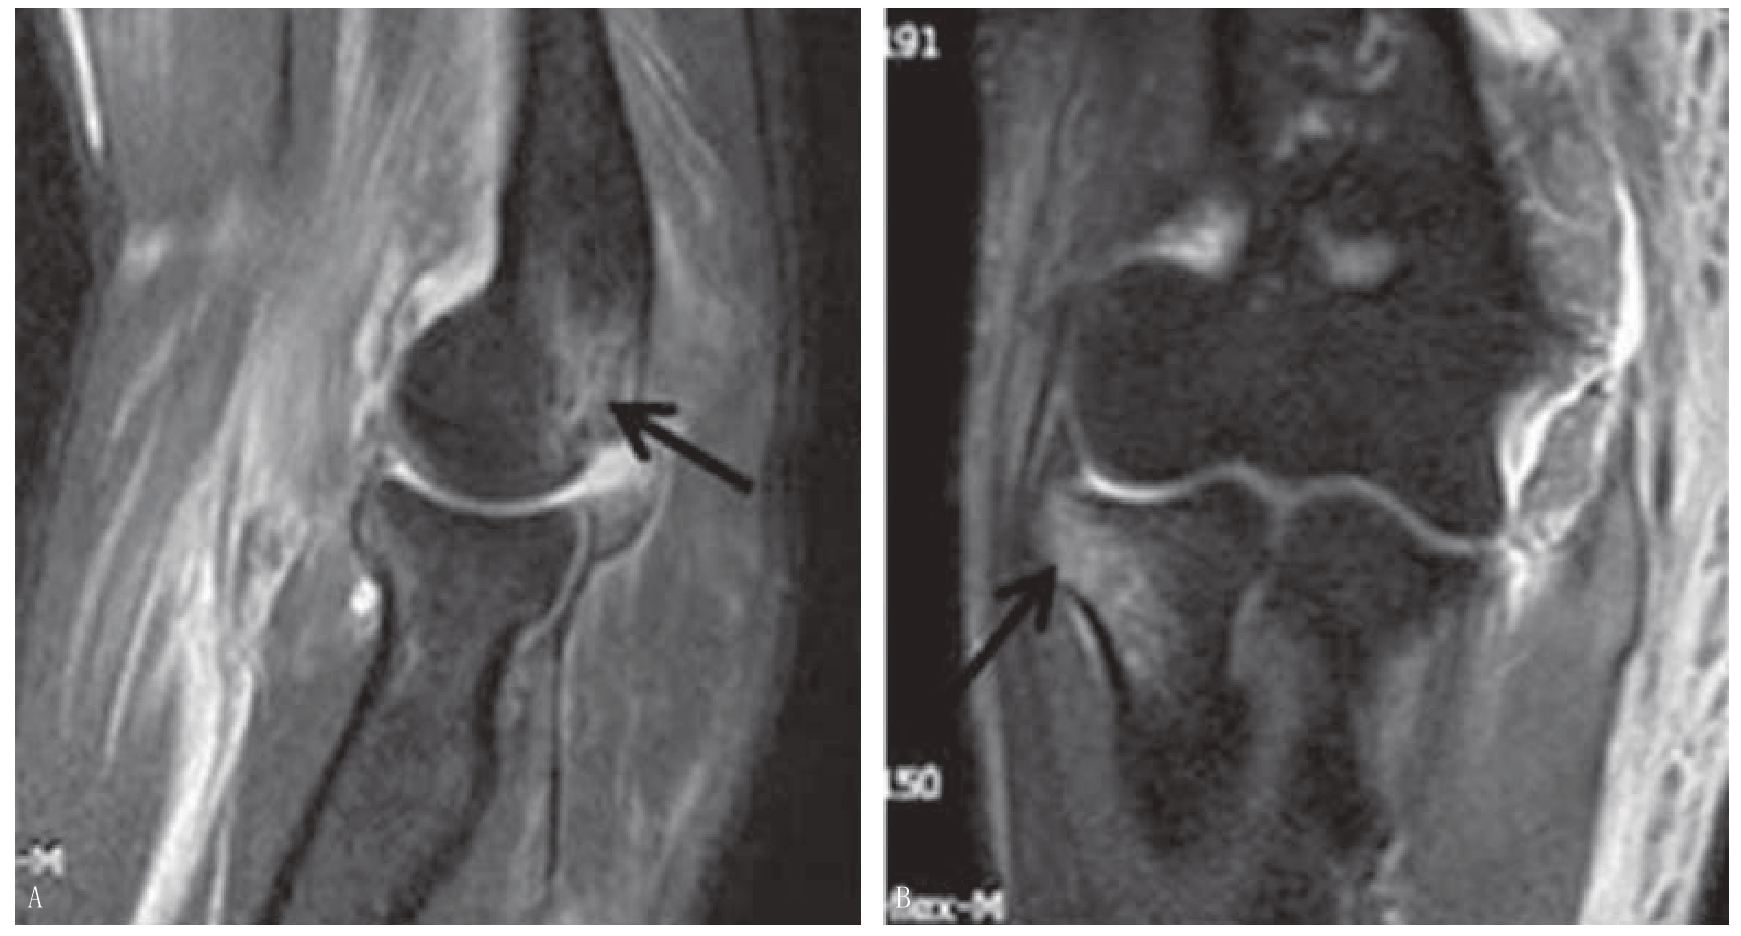

影像学辅助检查方面,肘关节脱位首先需要一张高质量的X线片,由于拍摄时患者体位限制,正侧位片的骨性结构常会重叠,二维影像难以了解损伤状态时,CT扫描就有必要完成,以确定损伤类型,同时排除可能合并的骨折,有助于做好治疗计划。MRI检查是否必要存在争议,多数学者认为并非必须,但MRI确可帮助认识软组织的损伤部位和严重程度,并可通过骨与软骨的损伤特点(主要为骨挫伤)进一步认识损伤机制和脱位的分类(图5—2)[9]

图5—2 MRI检查

A.MRI可以显示骨挫伤(左图黑箭头);B.MRI同时可以显示损伤的韧带等软组织结构(右图黑箭头),有助于推断损伤机制及治疗方案的选择